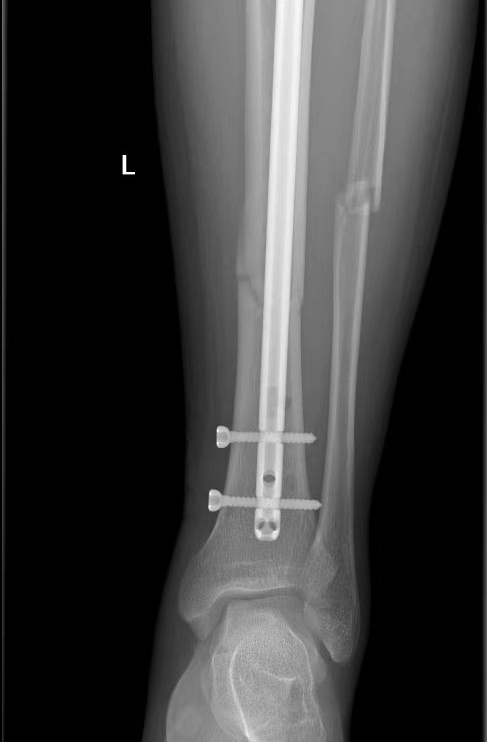

患者左胫骨骨折手术同样采用微创经皮髓内钉固定的方法,这种术式减轻了患者创伤,但对术者的技术要求较高。李清主任从患者胫骨上端切开一个小切口,小心翼翼地把髓内钉置入胫骨内,复位固定胫骨,C 臂机透视证实,骨折对位对线良好,内固定物位置适当,手术成功。